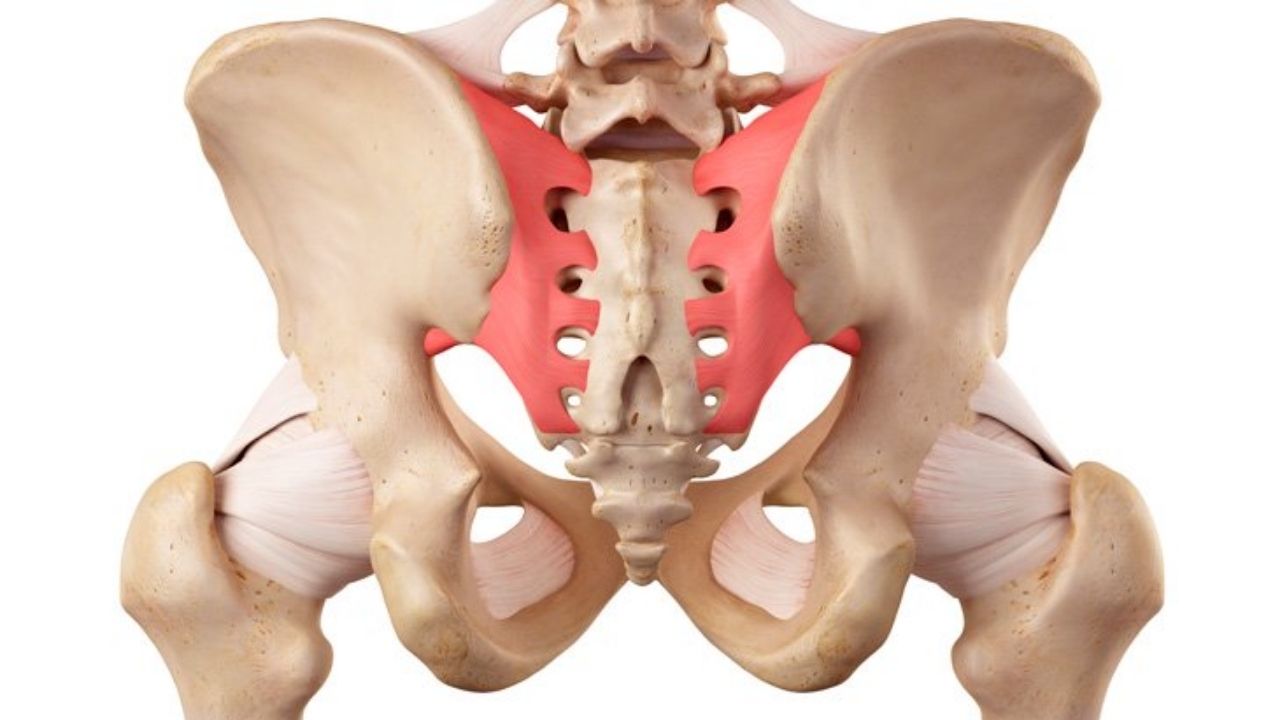

Atuação em hérnia de disco, fraturas da coluna, escoliose, estenose vertebral e processos degenerativos.